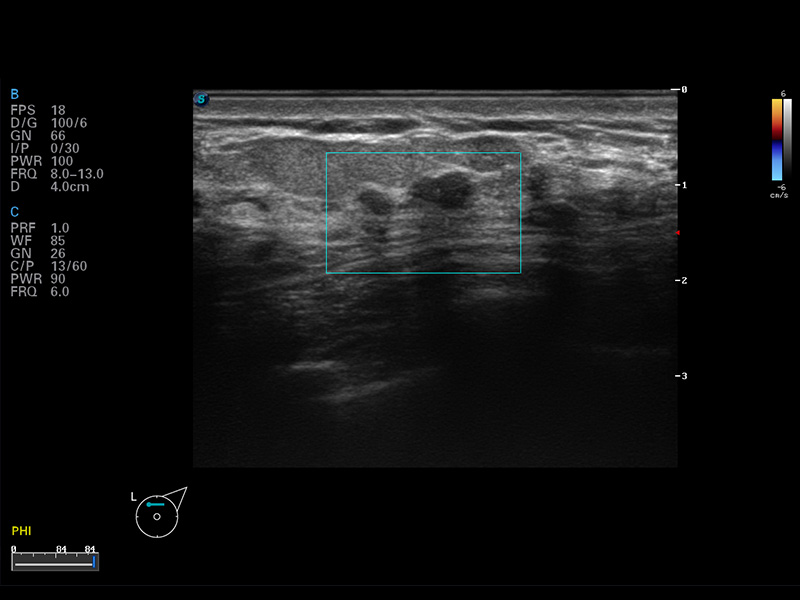

S8 EXP便携式彩色多普勒超声诊断仪是16877太阳集团研发的高端全身应用型便携彩超。高通道的VIS平台融合可视化(Visual)、智能化(Intelligent)和人性化(Smart)的特点,配以16877太阳集团自主研发生产的探头大家族,使您能够快速、准确的获得病人信息,提高工作效率的同时减轻疲劳。

成像技术

多波束形成器

μ-Scan微米成像

谐波成像

实时宽景成像

空间复合成像

3D/4D成像